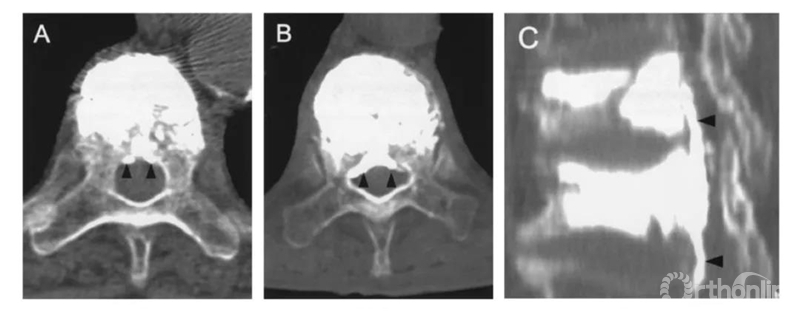

根据渗漏的途径及CT表现,将骨水泥渗漏分为三种类型:B经椎旁静脉渗漏;S经节段血管渗漏;C经皮质缺损渗漏。

B经椎旁静脉渗漏:在椎体后缘相对对称分布。一般不超过椎管横径的1/3。矢状位CT显示会向头尾侧弥散。

S经节段血管渗漏:沿节段静脉走行弥散。轴位CT呈水平走行。有时会顺着血管上下弥散,矢状面呈垂直或斜行。

C经皮质缺损渗漏:顺着缺损区到处跑,椎体周围、椎管内、椎间盘,哪里有路往哪走。

比如这例,侧位X片看骨水泥在椎弓根里,可CT一扫发现已经渗漏进入椎管。

侧位X片看骨水泥在椎体里,CT显示渗漏进入椎管。

侧位X片看骨水泥在椎间孔周缘,CT显示渗漏进入椎管,累及椎间孔。